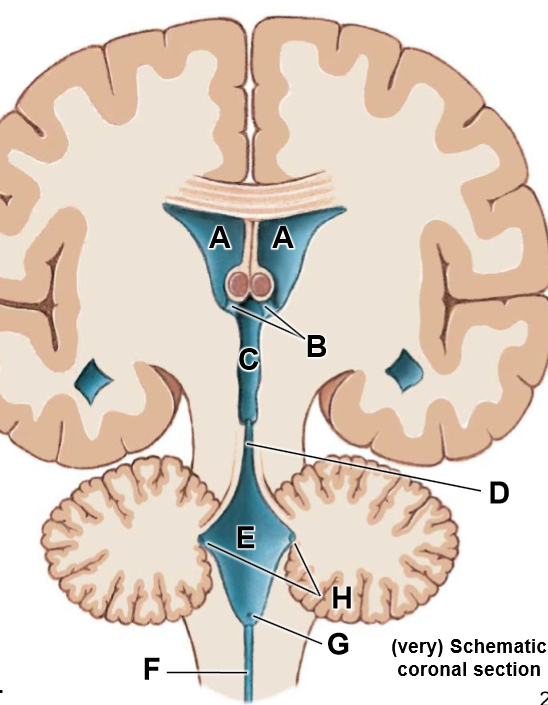

A-F

A: R/L lateral ventricles

B: Intraventricular foramen

C: Third ventricle

D: Cerebral aqueduct

E: Fourth ventricle

F: Central canal

G: Median aperture

H: Lateral apertures

__________ are associated with the cerebra hemispheres

Bilaterally paired lateral ventricles

______ is associated with the diencephalon

third ventricle

______ is associated with the midbrain

Cerebral aqeduct

_______ is associated with the pons, medulla, cerebellum

fourth ventricle

The ________ is associated with the spinal cord

central canal